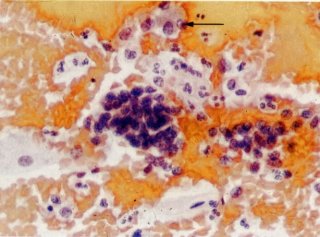

41. Células endometriais: migração. Seguindo à menstruação, as células endometriais ficam com a aparência de histiócitos, e, em alguns casos, essas células são vistas fluindo para fora mais habitualmente de um agrupamento glandular ou estromático, como ilustrado neste campo. (X 160)